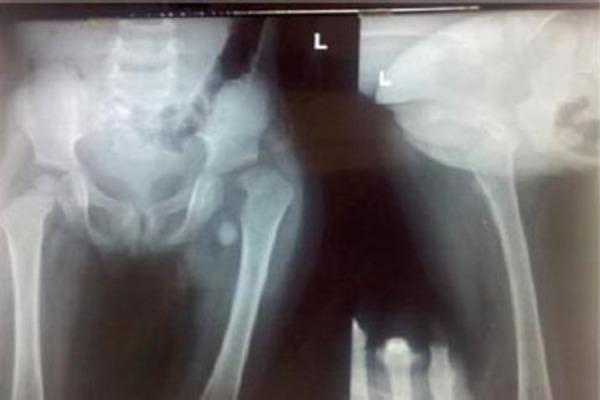

Complete Traumatic Separation of Proximal Femoral Epiphysis in A 2 Year Old Child.

Hip fractures are very common in adults, but are rare in children, comprising less than 1% of all pediatric fractures. Separation of the proximal femoral epiphysis can occur in a child with a traumatic hip dislocation and an open epiphysis. Regardless of the mechanism of proximal femoral epiphyseal separation, the prognosis is poor secondary to the development of osteonecrosis.

CASE REPORT

Here we are reporting a case of complete separation of the proximal epiphysis of the femur in a 2 year old female child. She was treated by open reduction and internal fixation by a single k-wire of proximal femoral epiphysis. Regular follow up showed fusion of proximal femoral epiphysis at about 3 months of post operative period. After 8 months of follow up she can stand and walk without support. Long term outcome is awaited.

Traumatic separation of the proximal femoral epiphysis is a rare but devastating injury because osteonecrosis occurs in most cases. In our study we found fusion of the proximal femoral epiphysis to the neck after 3 months of postoperative period. But to comment upon the final outcome a long follow up is awaited.